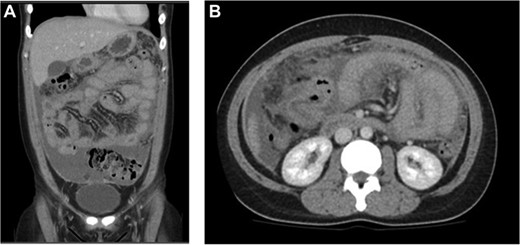

A 28 -year-old lady from the Philippines presented with a 1-month history of right upper quadrant pain and suprapubic pain, bloating and night sweats. Her background history includes chronic hepatitis B for which she has ongoing follow-up with a liver physician. On examination, she had normal observations; her abdomen was distended with mild tenderness throughout. Her blood tests revealed a normal white cell count and liver functions, and the liver screen was consistent with chronic hepatitis B infection. Her CA125, however, was elevated at 218 units per millilitre (U/mL). The other tumour markers, including carcinoembryonic antigen, carbohydrate antigen 19.9 and alpha fetoprotein, were all normal. An ultrasound of her abdomen showed a 16 mm left para-ovarian cyst, thickened fallopian tubes and moderate free fluid. She subsequently had a computed tomography (CT) scan, which showed ascites with diffuse peritoneal thickening encasing small bowel loops (Fig. 1A and B). The gynaecological team was consulted as there was initial concern of a possible ovarian cancer. She had an ascitic tap, which showed lymphocytic rich fluid, with no evidence of malignancy. The patient also had no previous contacts with TB, and her TB screening 6 years ago for her visa was negative.

(A) Coronal and (B) axial views: diffuse peritoneal thickening with moderate ascites and encasement of small bowel loops.